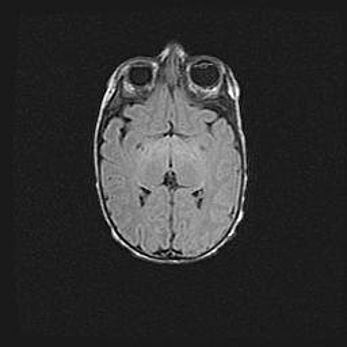

Церебральная ишемия II.

Возраст: 7 дней

Вес: 3350 г

Пол: женский

Окружность головы: 35 см

Срок гестации: 39 недель

Ишемия головного мозга – это состояние, которое развивается в ответ на кислородное голодание вследствие недостаточного мозгового кровообращения. У новорожденных она является следствием дефицита кислорода, что ведет к метаболическим расстройствам различной степени тяжести в тканях головного мозга, в том числе к развитию коагуляционных некрозов и гибели нейронов.